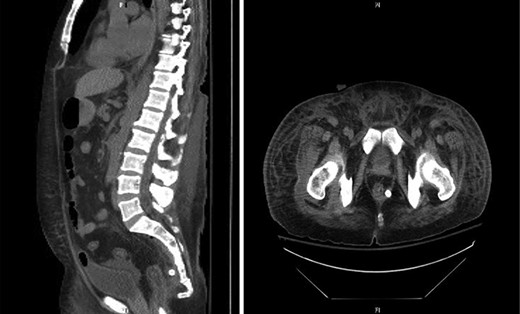

CT abdomen and pelvis showed a rectal perforation with perirectal pelvic inflammatory soft tissue/phlegmon containing air-fluid level that infiltrated into the presacral space extending up through the sciatic notch into the right gluteus medius and minimus muscle (Figs 1 and 2). Chronic inflammatory changes of the transverse colon and left colon were also present. The patient was taken to the operating room (OR) for examination under anesthesia. A flexible sigmoidoscopy was passed up into the distal descending colon, which showed discontinuous areas of ulcerated mucosa with cobble-stoning notable for active Crohn’s disease and a diffuse pseudomembrane reminiscent of C. difficile colitis (the negative C. difficle assay). A rectal perforation was noted just above the dentate line. The incision was enlarged and the presacral space was entered with a flexible sigmoidoscope. There was extensive necrosis of the presacral tissue with copious amounts of purulent fluid. The abscess was evacuated, and all loculated fluid collections were drained. The cavity was then irrigated via the sigmoidoscope. Once satisfactory drainage was achieved, a Malecot catheter was then inserted through the rectal perforation into the presacral space. A laparoscopic diverting loop ileostomy was then created to allow for healing.

CT sagittal view showing contrast (white) entering the lumen of presacral abscess and rectus abdominis muscle pushed anteriorly.

CT axial view showing tract from presacral space through the sciatic notch to thigh muscles.